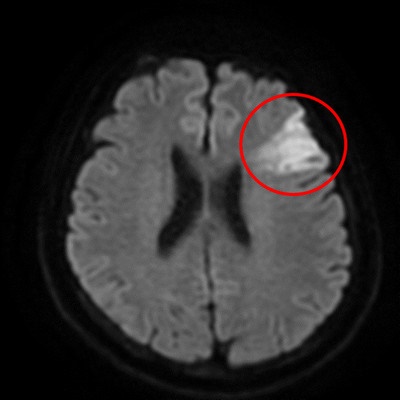

腦中風臨床表現包括平衡感、視力或手腳肌力下降,或是臉部或嘴角的歪斜、口齒不清等,甘女士的兒子因職業原因相當警覺,察覺到媽媽的症狀疑似腦中風,雖右手和右腳尚能行動,但握力明顯變差,因此果斷將病人送醫。救護車抵達急診後,醫療團隊立即為病人做電腦斷層檢查,排除出血型腦中風,並做核磁共振,發現左腦有明顯發亮區域,以及缺少了左側內頸動脈的顯影,即確認是左腦急性腦塞與左側內頸動脈完全阻塞。

急診隨即會診神經外科團隊做腦血管內取栓術,利用介入技術將阻塞腦部大血管的血塊取出,改善血流循環,降低腦組織受損的範圍,在病人抵達醫院90分鐘內就完成了取栓治療。取出血栓、打通大血管後,甘女士的意識及說話方式恢復清晰,右半身肌力也已恢復正常,能夠自如下床行動。她表示,很慶幸兒子發現症狀後當機立斷叫救護車,直接將她從花蓮南區送往花蓮慈院,也感恩醫療團隊二十四小時待命的高效率,不僅救回她一命,也沒有在腦部留下不可逆的神經損傷。